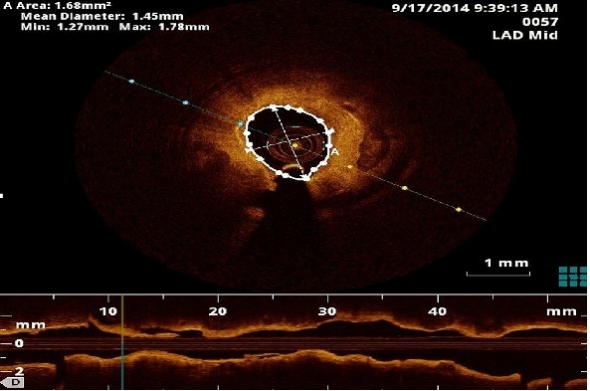

Qual a localização das zonas de um vaso sanguíneo com maior risco de reestenose após a aplicação de um stent farmacológico? Sirolimus ou Paclitaxel, qual o mais eficaz? Qual a posição do stent farmacológico com melhores resultados?

Estas são algumas das questões colocadas em cardiologia para as quais a matemática pode contribuir na procura de respostas.

Nesta palestra ilustramos como o diálogo interdisciplinar entre a cardiologia e a matemática pode encontrar solução para questões médicas.